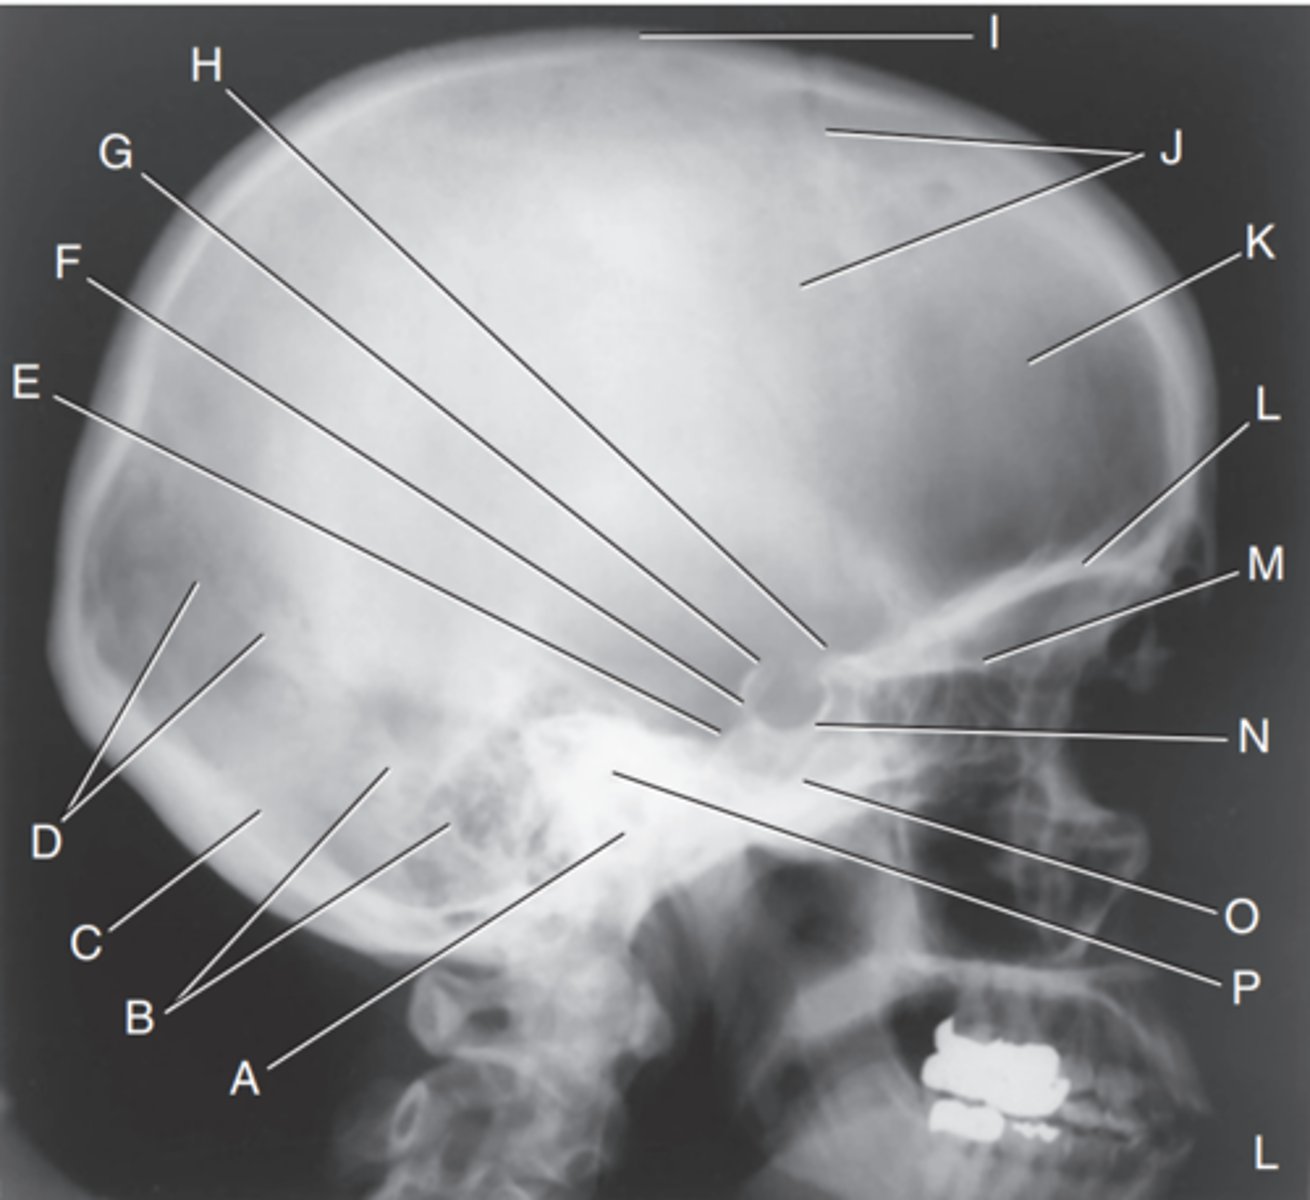

EAM

Label A

Mastoid portion of temporal bone

Label B

Occipital bone

Label C

Lambdoidal suture

Label D

Clivus

Label E

Dorsum sellae

Label F

Posterior clinoid processes

Label G

Anterior clinoid processes

Label H

Vertex of cranium

Label I

Coronal suture

Label J

Frontal bone

Label K

Orbital plates

label L

Cribriform plate

Label M

Sella turcica

Label N

Body of sphenoid (sphenoid sinus)

Label O

Petrous portion of temporal bone

Label P